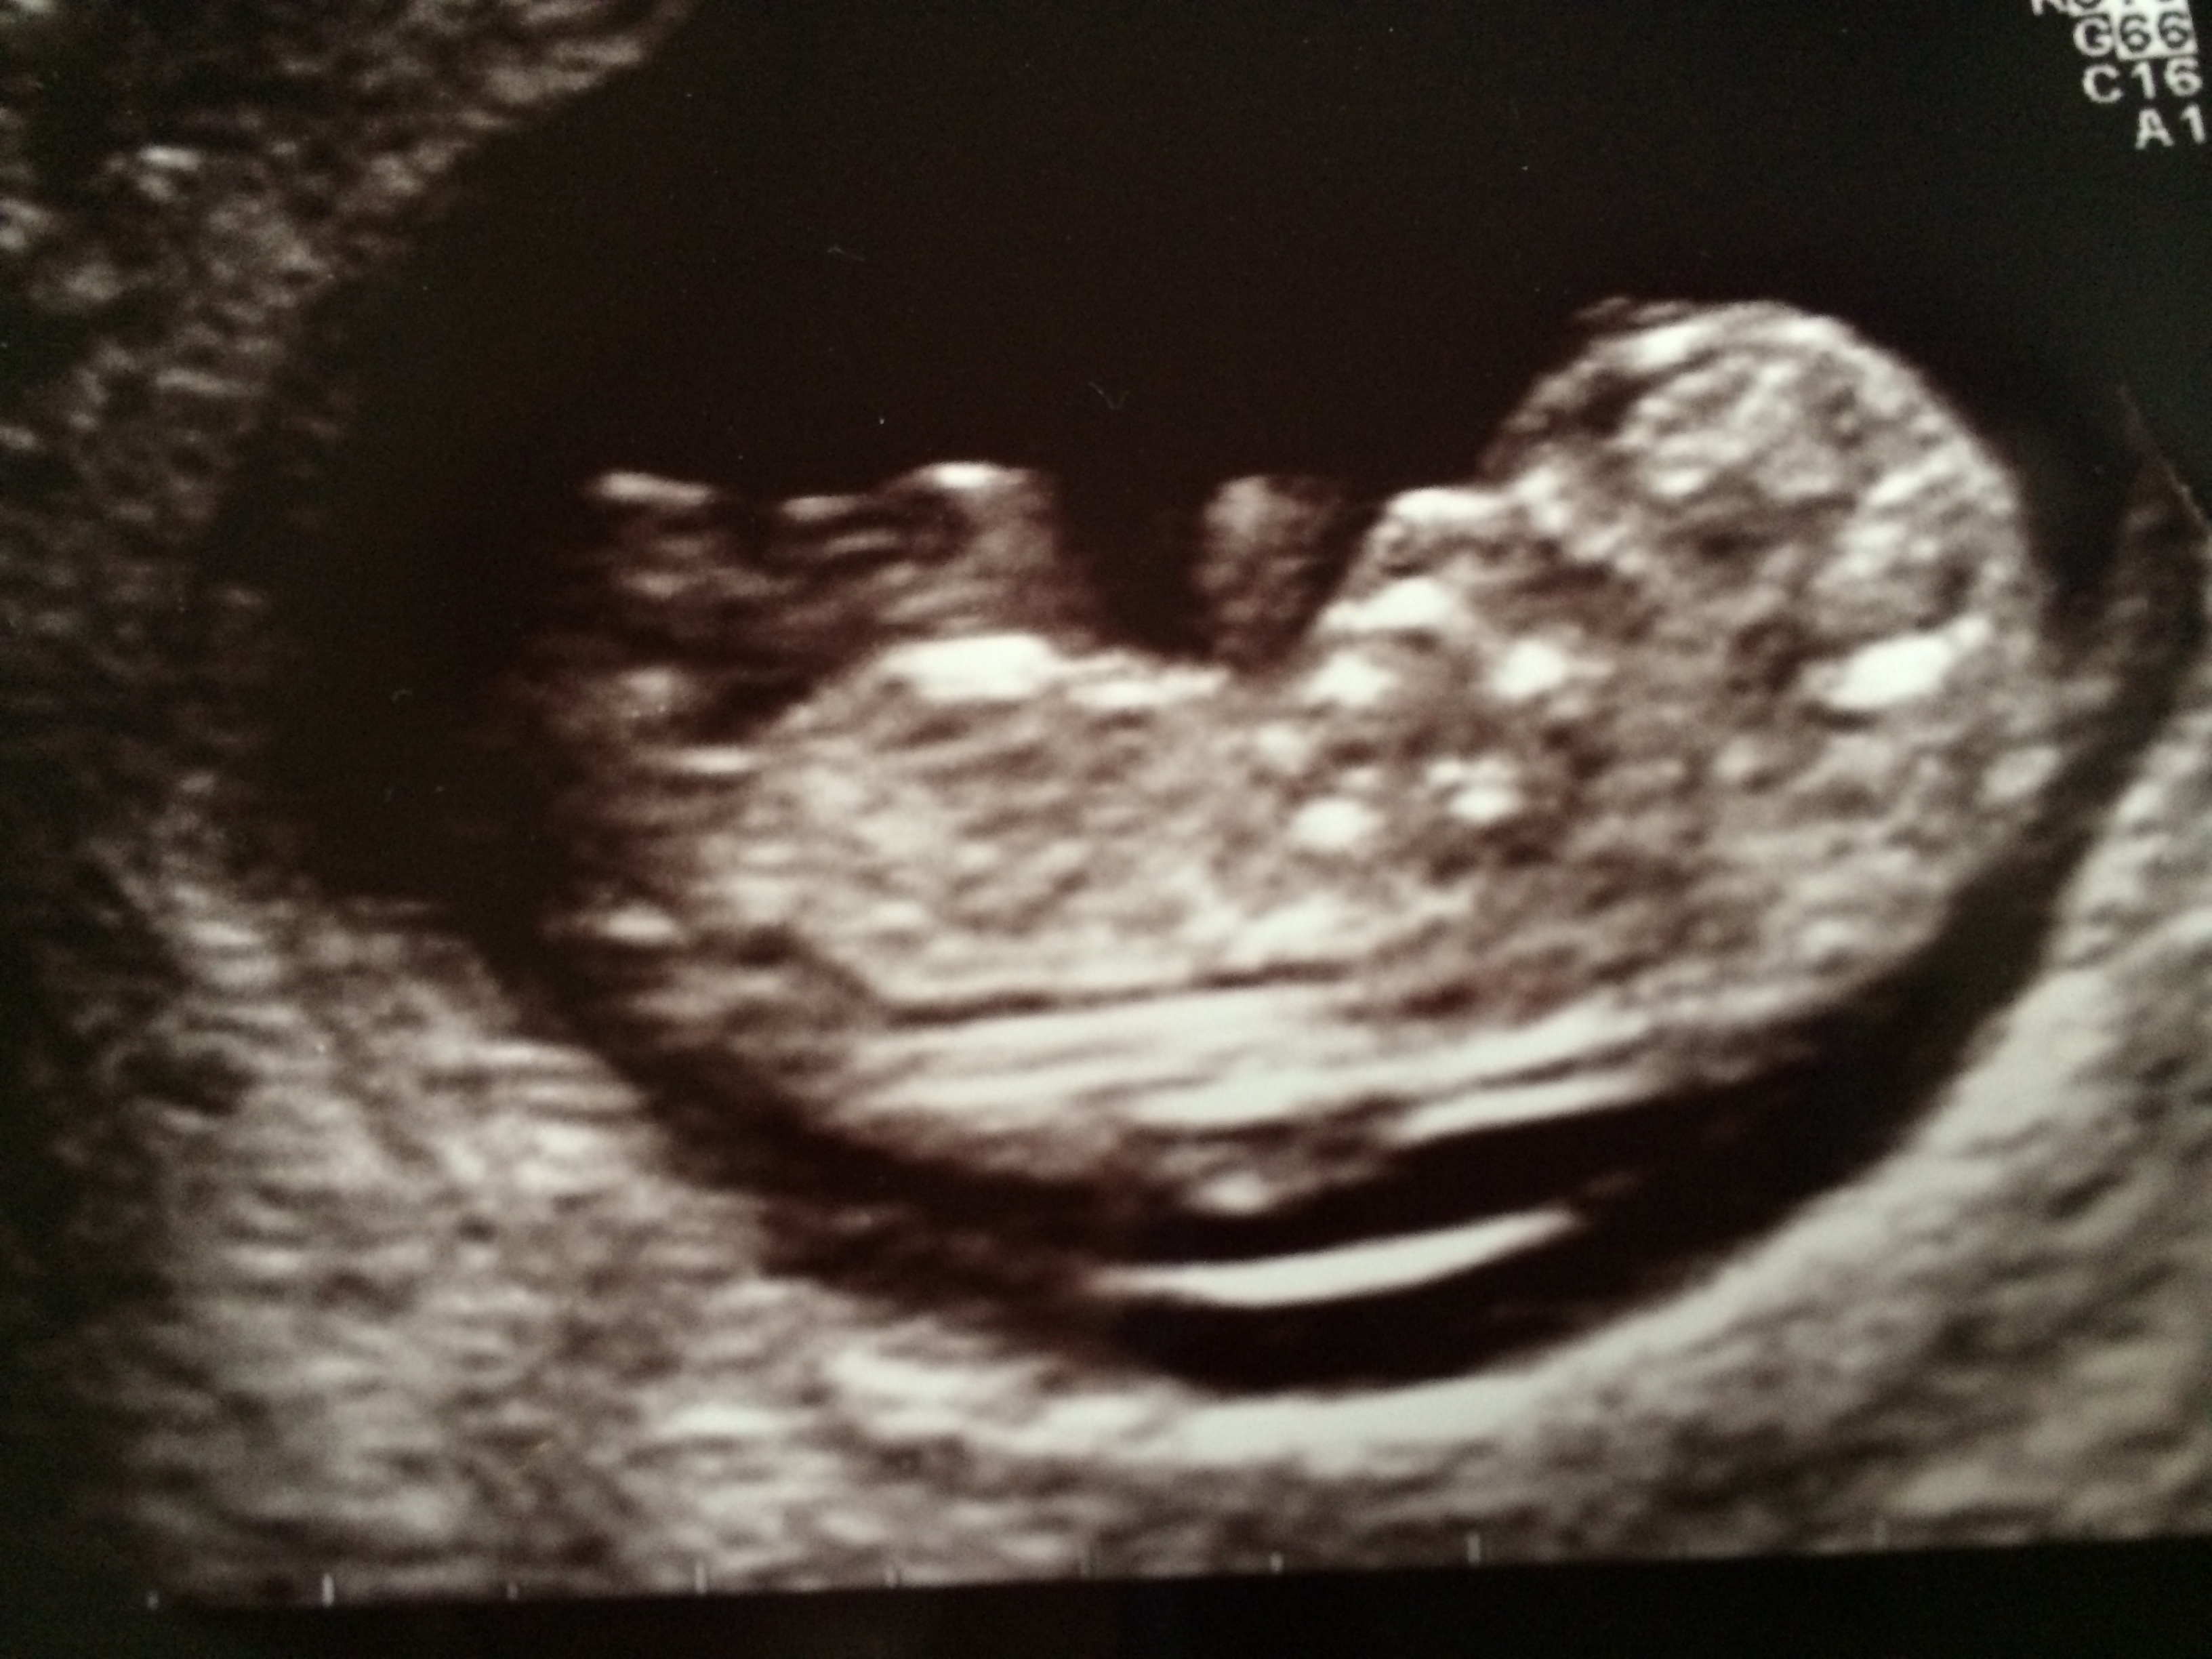

Attachment 17663

Hmm... although it is a little early I think I'm leaning boy (75%) - congrats x

Too early to tell sorry xx

Lookalike a boy but too early.

I agree....too early but it does look like a little boy nub starting to form :)

It's 50/50 in the 11th weeks, before the 12 week the nub is pretty much the same.